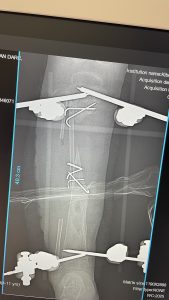

Und dies das Ergebnis nach 2-stündiger Operation.